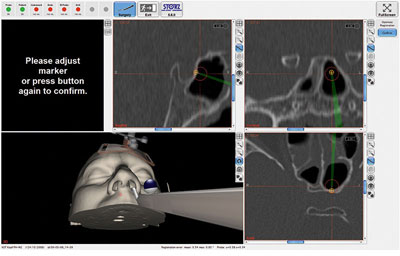

In endoscopy, the surgical procedure is chosen based on a combination of visual information supplied by the endoscope, the surgeon's anatomic knowledge and experience, and preoperative radiology data. However, this requires an optimal endoscopic image as well as precise orientation within the surgical field. Extensive pathologies as well as scarring and changes resulting from previous surgeries can significantly complicate the correct identification of the surgical site and hence jeopardize the patient's safety.

In such cases, surgeons can greatly benefit from support in spatial orientation. In ENT and skull base surgery, the KARL STORZ optical and electromagnetic navigation systems are excellent tools for this purpose. The position of the instruments is constantly measured either optically, through highly reflective glass spheres on the instruments, or electromagnetically through microcoils integrated in the instrument tip.

ENT Navigation Software 5.6.0 with Intraoperative Manual Registration RefinementThe new software tool for precise navigation Manual registration refinement following patient registration using landmarks or surface matching can be activated while navigation is in progress. Navigation is thereby not interrupted and the navigated instrument continues to be displayed. Following activation, an additional landmark can be set to adjust the registration accuracy. Special Features: